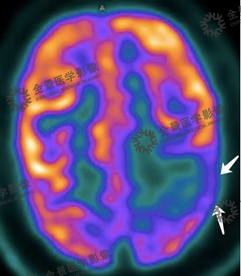

病史:患者女性19月,出生40天起开始癫痫发作,口服药物治疗中,刚开始时5个月内发作明显减少,但脑电图检查仍无异常,5个月后发作增加,增大药物剂量后效果不佳。遂来我中心进行PET/CT检查,结果如下:

右侧额顶颞枕叶皮质较对侧薄,FDG代谢较对侧减低。